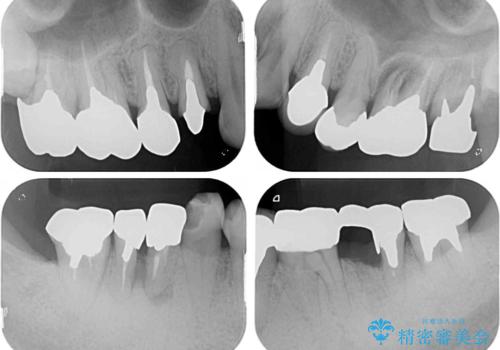

折れてしまった奥歯 インプラントによる補綴治療

- 奥歯に違和感を感じており、抜歯の必要性を感じて来院された患者様です。

診査の結果、5本の奥歯を抜歯してインプラントによる補綴治療が必要と診断されました。

患者様が違和感を感じていない左下の奥歯の治療は今回は見送り、それ以外の治療が必要な奥歯を治療することとしました。